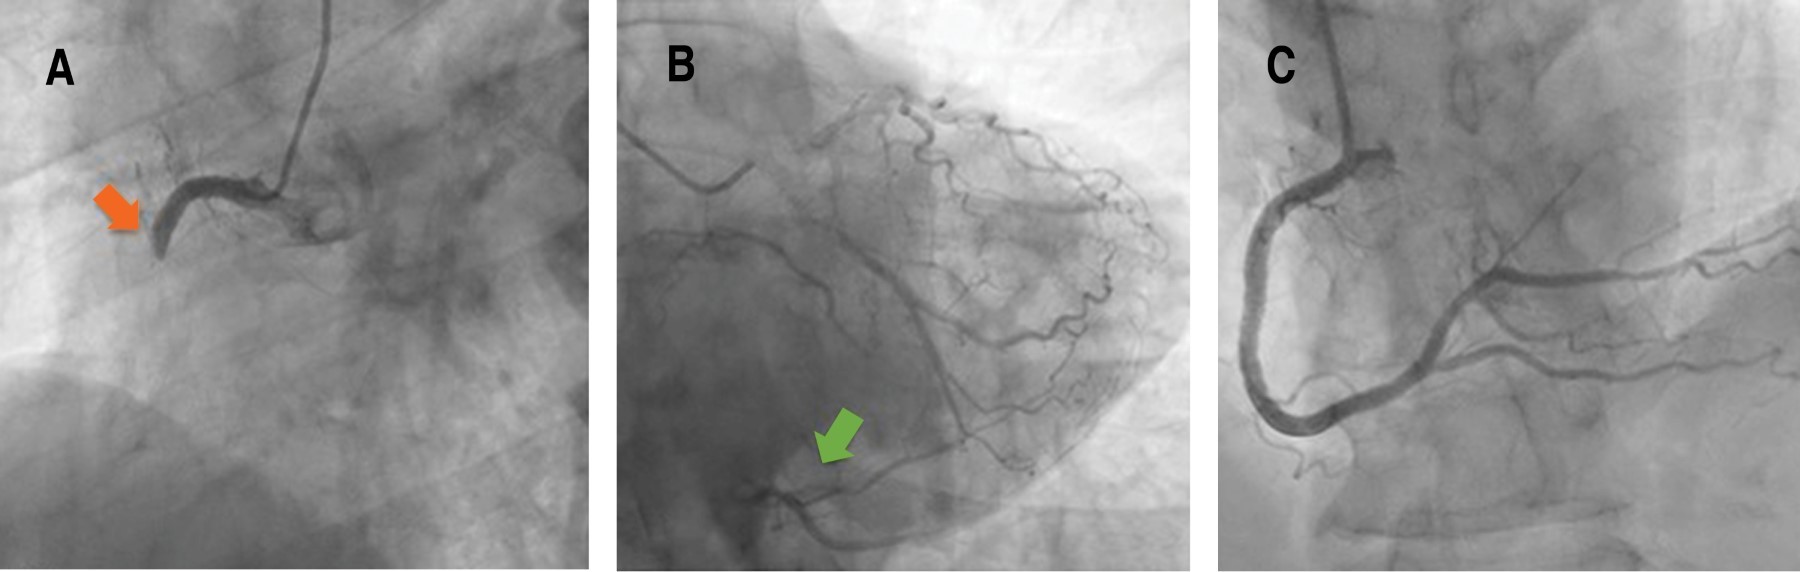

Caso clínico: paciente de 57 años que consultó por dolor torácico sugestivo de angina, con un electrocardiograma (ECG) que mostraba un bloqueo de rama derecha (BRD) no presente previamente, con las correspondientes alteraciones de la repolarización en contexto de bloqueo de rama sin cumplir criterios de isquemia. Por persistencia de angina a pesar del tratamiento se decidió realizar coronariografía emergente objetivando una oclusión trombótica aguda de la arteria coronaria derecha con buena circulación colateral (CC) heterocoronaria desde el árbol coronario izquierdo, el cual no presentaba lesiones significativas. Después de la revascularización, la angina desapareció progresivamente y se resolvió el BRD. Dada la buena CC heterocoronaria del territorio infartado, el tamaño del infarto fue menor de lo esperado y esto justificaría la escasa expresividad del ECG. Conclusión: el infarto de miocardio con oclusión aguda de una arteria coronaria debe tenerse en cuenta en pacientes con angina persistente a pesar del tratamiento y que el ECG no muestre las anomalías típicas.

Figura 1